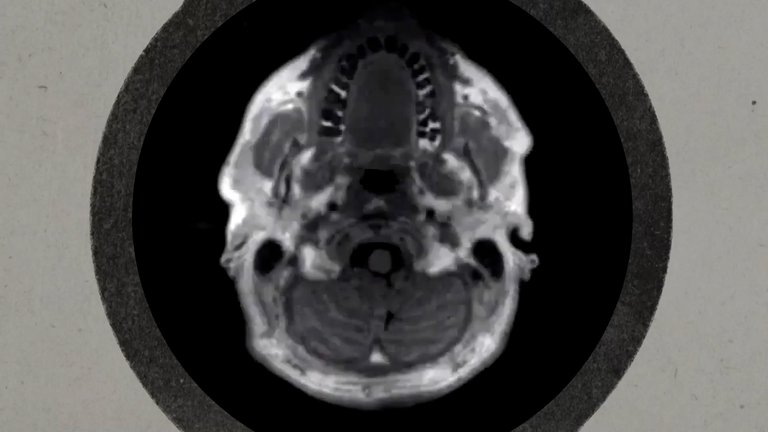

Se considera que los adolescentes alcanzan la madurez reproductiva durante la pubertad, y entre los 17 y 21 años los jóvenes ya son físicamente adultos. Pero no ocurre lo mismo con el cerebro, ya que éste continúa desarrollándose hasta los 25 o 30 años.